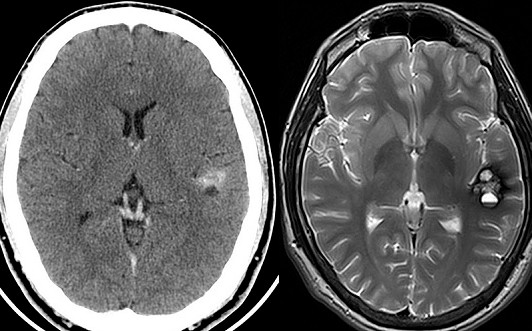

МРТ или КТПо этим причинам различаются и диагностические области применения двух видов томографий. МРТ лучше всего «видит» ткани, имеющие в своем составе большое количество атомов водорода -  подходит для выявления патологий мягких тканей, суставов, хрящей, сухожилий, паренхиматозных органов, сосудов, головного мозга в большинстве случаев. Из-за низкого содержания водорода в костных тканях МРТ не используется для их диагностики.

КТ, напротив, лучше визуализирует полые органы, кости и структуры, заполненные воздухом, поэтому методика успешно используется для оценки состояния легких, бронхов, опорно-двигательной системы.

Голова

МРТ рекомендуется проводить:

КТ дает лучшие результаты в случае: